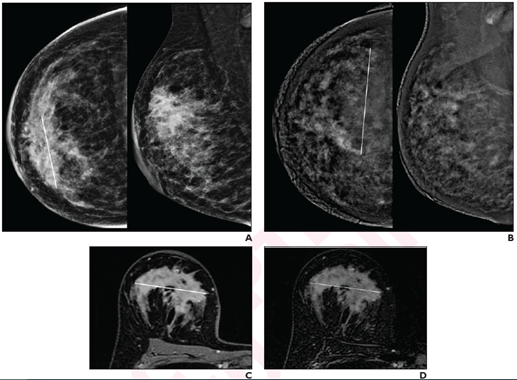

41-year-old woman with invasive ductal carcinoma (G2, luminal B) of right breast. A, CC (left) and MLO (right) low-energy images from pre-NAT CEM performed on 25th day of luteal phase show a 60-mm architectural distortion (line on CC) in the central portion of the right breast. B, CC (left) and MLO (right) recombined images from pre-NAT CEM show marked background parenchymal enhancement, hindering lesion evaluation; 90-mm non-mass regional enhancement (line) was described. C, Axial fat-saturated T1-weighted unenhanced MR image shows a 70-mm hypointense irregular mass (line) with not circumscribed margins in the central portion of right breast. D, Axial fat-saturated T1-weighted post-contrast MR images shows corresponding fast initial enhancement (line) with delayed plateau.

“After NAT for breast cancer, CEM and MRI yielded comparable assessments of lesion size (both slightly overestimated vs pathology) and RECIST categories, and no significant difference in specificity for pathologic complete response,” wrote corresponding author Rubina Manuela Trimboli of IRCCS Humanitas Research Hospital in Milan, Italy. Noting that MRI had higher sensitivity for pathologic complete response, “delayed CEM acquisition may help detect residual ductal carcinoma in situ (DCIS).”

Compared with pathology, post-NAT CEM, MRI, and delayed CEM systematically overestimated residual tumor size by 0.8 mm, 1.9 mm, and 1.2 mm, respectively. For detecting pathologic complete response by post-NAT imaging, sensitivity and specificity were 81% and 83% for CEM, 100% and 86% for MRI, and 81% and 89% for delayed CEM.